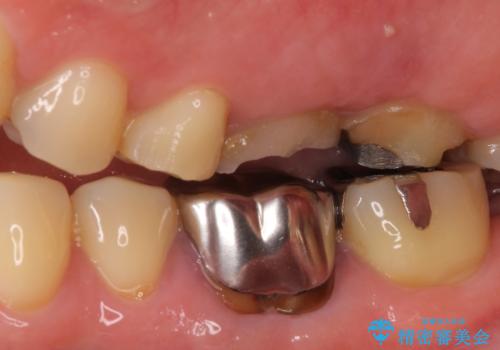

- 長い間虫歯を放置しており、違和感を感じ始めてきたので治療を開始したいと来院された患者様です。

極力抜歯が回避する方法を選択して診察を開始しましたが、1本は保存困難と判断されたため、フルジルコニアブリッジによる補綴治療を行うこととしました。

歯根の先端に病変の認められた奥歯は、補綴前に根管治療を行うこととしました。

違和感を感じていた歯は虫歯が非常に大きく、骨に到達するほどの穴が空いていました。